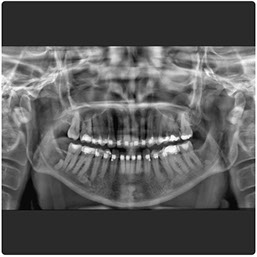

El Eagle 2D Pan/Tele ofrece todos los exámenes en el perfil panorámico (panorámica estándar, senos maxilares, baja dosis, bitewing, ATM, ortogonalidad perfeccionada, panorámica infantil y bitewing ortogonalidad perfeccionada) y todos los exámenes en el perfil cefalométrico (Posteroanterior, Antero-posterior, 45 Grados, Lateral, Carpal, PA de Walters, Axial Bazal, Hirtz).

La línea Eagle ofrece alta calidad de imagen, facilidad de operación, fácil posicionamiento del paciente y reúne lo mejor de la tecnología mundial en todas las funciones. El generador de rayos X de alta frecuencia reduce la exposición innecesaria del paciente. El sistema de microprocesado de alta velocidad y la mecánica precisa permiten la perfecta ejecución y repetición en imágenes 2D y 3D

Radiografía Panorámica Digital

Radiografía Panorámica